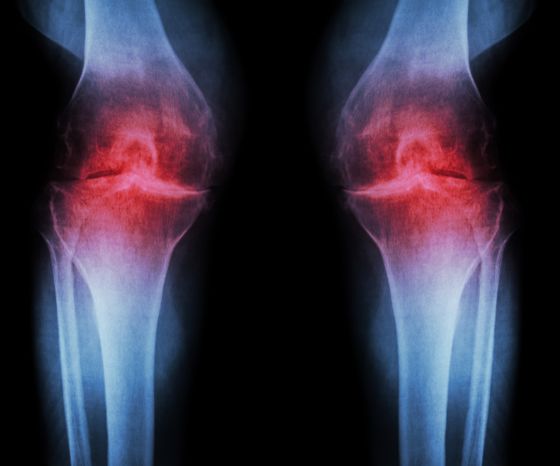

Một đặc điểm cổ điển của thoái hóa khớp gối là những thay đổi về mặt mô học về chất lượng và độ dày của sụn khớp. Sự suy giảm sụn khớp dẫn đến phì đại xương dưới sụn và hình thành gai xương ở rìa bề mặt khớp. Một hậu quả khác là tình trạng viêm mãn tính của mô hoạt dịch. Tất cả những thay đổi này dẫn đến bề mặt khớp không đều, xương to ra, bao khớp có thể dày lên và cuối cùng là phù khớp. Sự thu hẹp không gian khớp có thể nhìn thấy trên hình ảnh chụp X-quang, đó là lý do tại sao chúng ta còn nói đến “viêm xương khớp trên X-quang”.

Hệ thống phân loại được sử dụng phổ biến nhất cho bệnh thoái hóa khớp trên hình ảnh học là thang điểm Kellgren & Lawrence ( Kohn et al. 2016 ):

- Độ 0 : không có đặc điểm X quang của OA

- Độ 1 : nghi ngờ hẹp khe khớp và có thể có gờ xương

- Độ 2 : gai xương rõ ràng và có thể hẹp khe khớp trên phim chụp X-quang chịu lực trước sau

- Độ 3 : nhiều gai xương, hẹp khe khớp rõ rệt, xơ cứng, có thể biến dạng xương

- Độ 4 : gai xương lớn, hẹp khe khớp rõ rệt, xơ cứng nặng và biến dạng xương rõ rệt